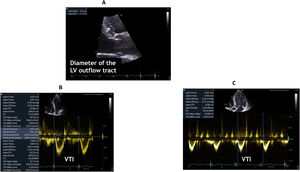

Cardiac output (CO)Measurement of CO remains a corner- stone in the hemodynamic assessment of critically ill patients and in particular in CS patients as decreased CO is often observed in such population. Several methods for determining CO have been described using both two-dimensional and Doppler echocardiography.15,16 Of these methods, the one using the left ventricular outflow tract (LVOT) and aortic valve as the conduit, is probably the most reliable and most commonly used as there is an excellent agreement with the reference CO measured by thermodilution in most situations 15 (Fig. 3B and C). The measurement of stroke volume (SV) is usually made at the LVOT. When using the TTE approach, the operator measures the LVOT diameter from the parasternal long-axis view immediately below the hinge point of the aortic valve leaflets (Fig. 3A). The LVOT area (cm2) is calculated from this diameter measurement using the formula:

Next, the operator places the pulsed wave Doppler (PWD) sample volume in the LVOT to measure the velocity time integral (VTI) of blood flow in the LVOT, using the five-chamber apical view. The SV is calculated as follows: